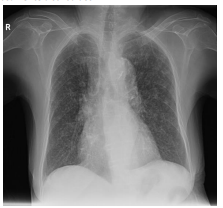

Uma mulher de 40 anos, com sintomas respiratórios e

emagrrecimento apresenta alterações em radiografia de

tórax,em posição póstero-anterior, compatíveis com padrão

miliar (imagem).

III. Representam micronódulos entre 2 e 3mm de diâmetro difusamente distribuídos